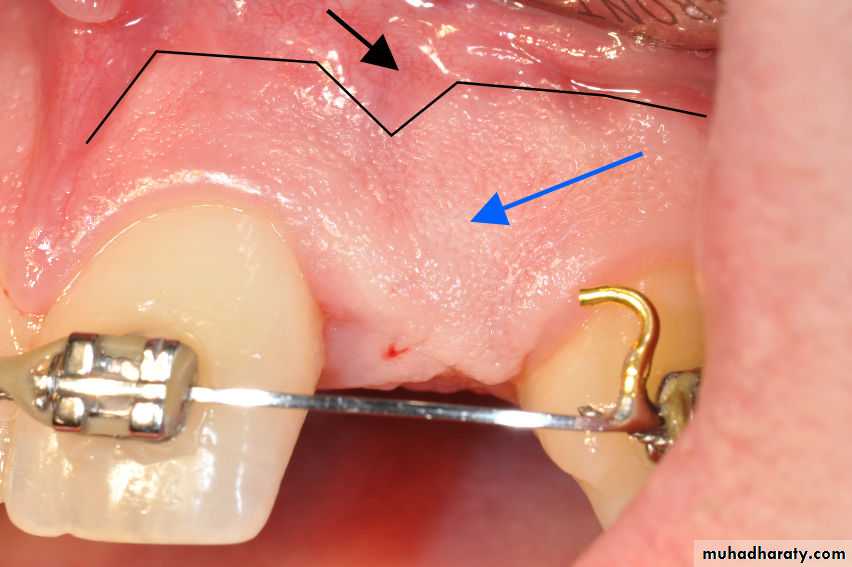

• Sinus

• Sinus orifice from a palatal periodontal abscess• Pinpoint orifice in the palate indicative of a sinus from a

• periodontal abscess.

• Probe extends into the abscess deep in the periodontium.